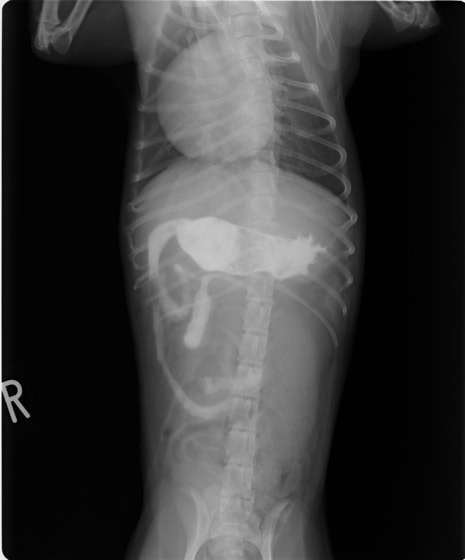

9歳 チワワ 4.8kg

主訴:2日前の夜に桃の種を飲み込んだとのこと。元気・食欲に問題はなく、嘔吐などの消化器症状もみられなかった。誤飲した当日に他院にて催吐処置を試みたが、吐き戻さなかったとのこと。

単純レントゲン検査:明らかな異常所見なし

消化管バリウム造影レントゲン検査:胃内にて異物の存在を疑う異常所見を認めた。

造影直後

内視鏡検査:内視鏡下にて、バスケット鉗子を用いて胃内異物を摘出。

異物内容:桃の種 (約4cm大 写真上)、とうもろこしの芯 (約2.5cm大 写真下)

本症例は、床に落としてしまった桃の種を誤飲していました。動物の体格に対して異物が非常に大きく、開腹手術となる可能性があった症例でした。また、桃の種と一緒に出てきたとうもろこしの芯は、日々のおやつとして与えていたものということでした。とうもろこしの芯は非常に硬く、小さく切って与えても消化されず、長期間胃内に残ってしまうことや腸閉塞の原因となる為、注意が必要です。